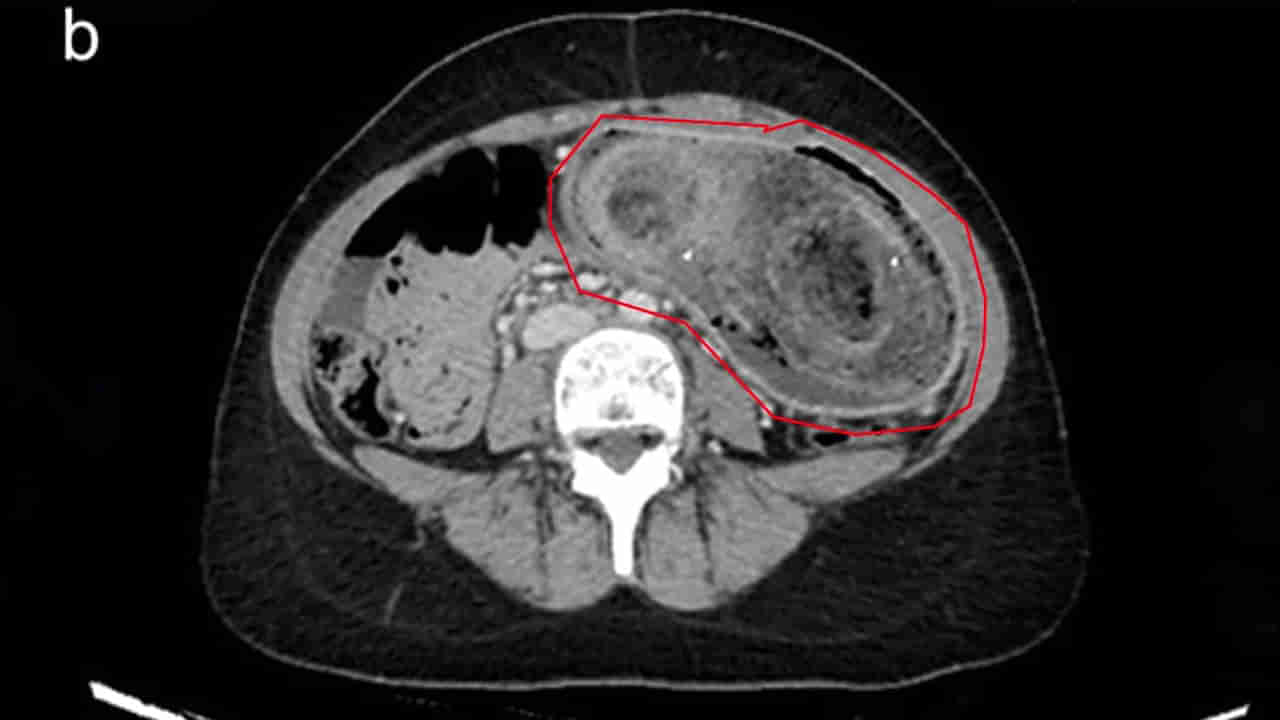

ఫలితంగా ఆ యువతి చాలా సంవత్సరాలుగా జుట్టును తినేది. డాక్టర్లు పరీక్షలు చేయగా.. ఆమె పొత్తికడుపులో ఉబ్బి కనిపించింది. ఆ ప్రదేశంలో వెంట్రుకల ముద్ద ఉన్నట్టు గుర్తించారు. ఆపై ఎండోస్కోపిక్ ద్వారా దాన్ని తొలగించారు వైద్యులు. మూడు గంటల పాటు ఈ శస్త్రచికిత్స జరిగింది. కాగా, చికిత్స చేసిన నాలుగు రోజుల తర్వాత ఆమెను డిశ్చార్జ్ చేయగా.. ఆ తర్వాత మానసిక నిపుణులతో కౌన్సిలింగ్ ఇప్పించారు.